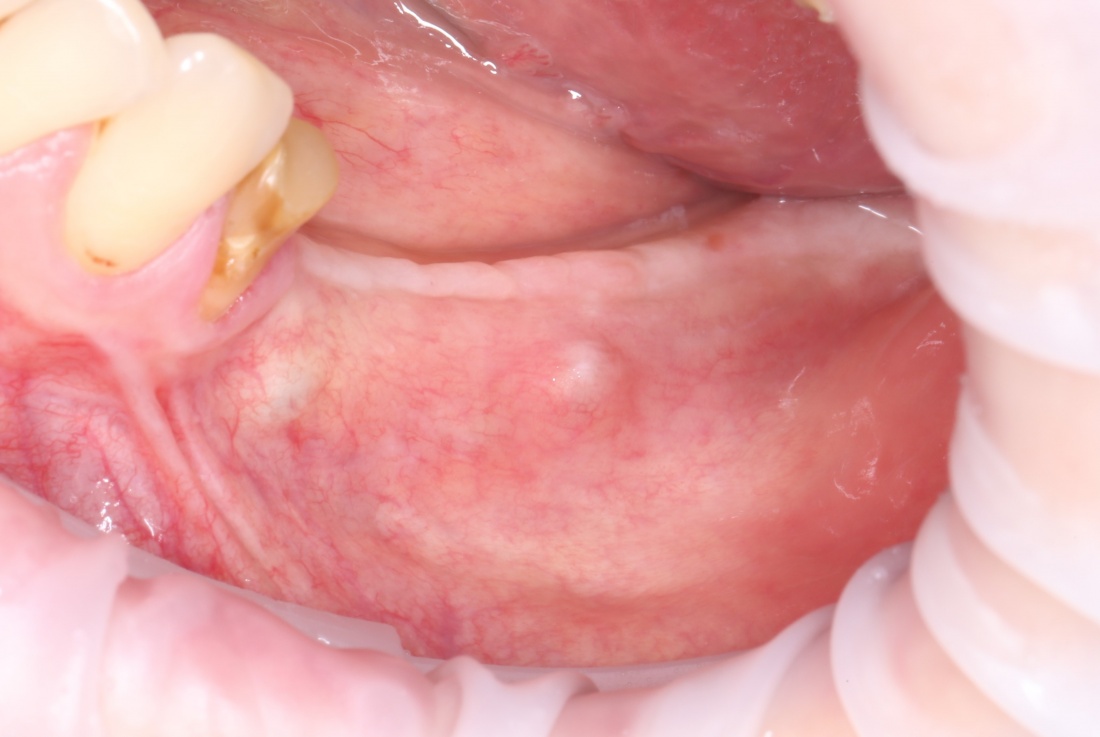

Простой. Надежный. Дешевый. Способ остеопластики.